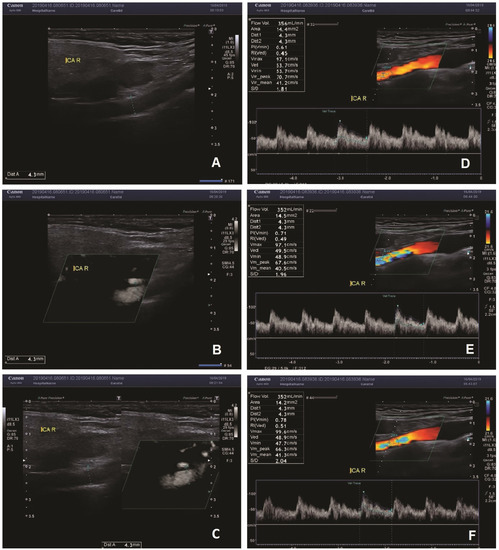

Figure 1.

(A–C)—the measurement of the diameter of the vessel with B-mode (A), SMI (B), combined B-mode/SMI (C). In all three measurements, the diameter of the vessel was 4.3 mm. (D–F)—measurement of the flow volume in the right ICA. The flow volume was 356 mL/min in one measurement (A), and 352 mL/min in two measurements (E,F).